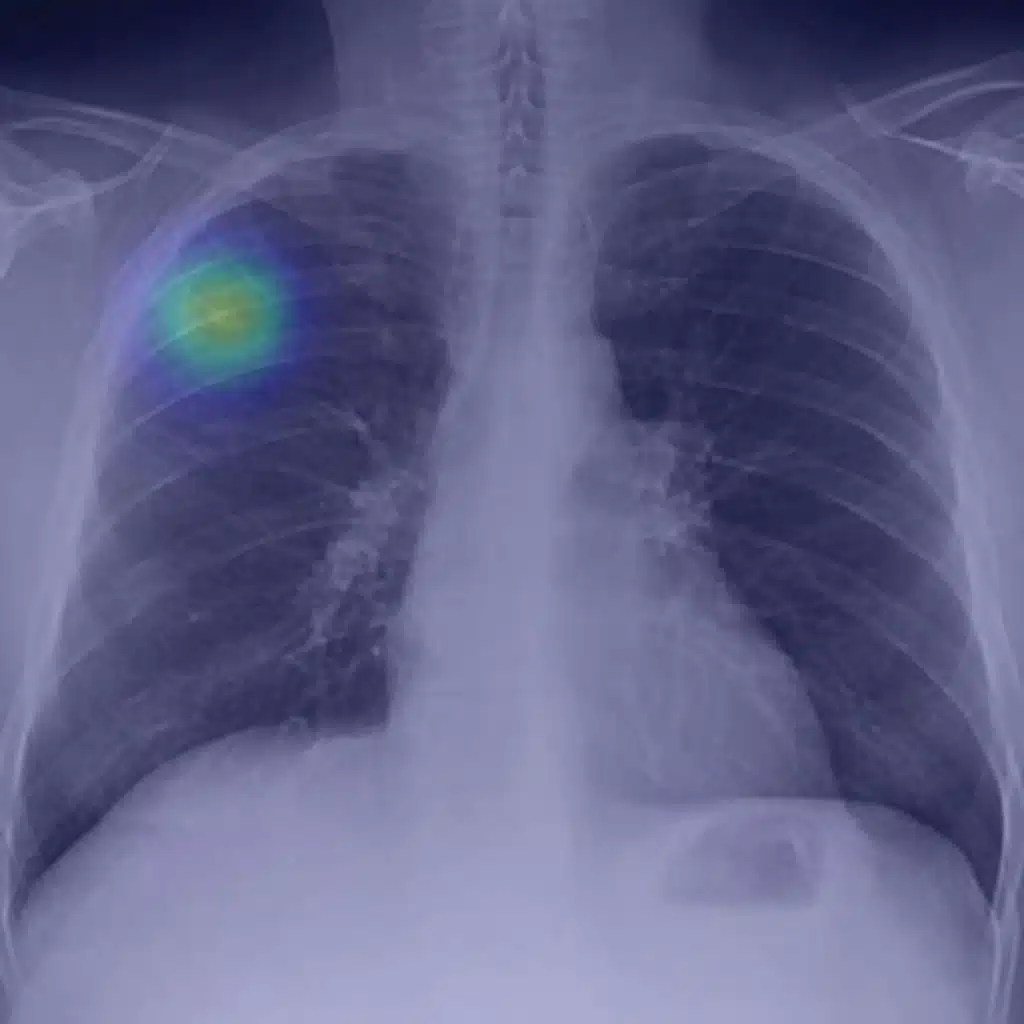

Interview with Puneeth Iyengar, MD, PhD, author of Accelerated Hypofractionated Image-Guided vs Conventional Radiotherapy for Patients With Stage II/III Non–Small Cell Lung Cancer and Poor Performance Status: A Randomized Clinical Trial